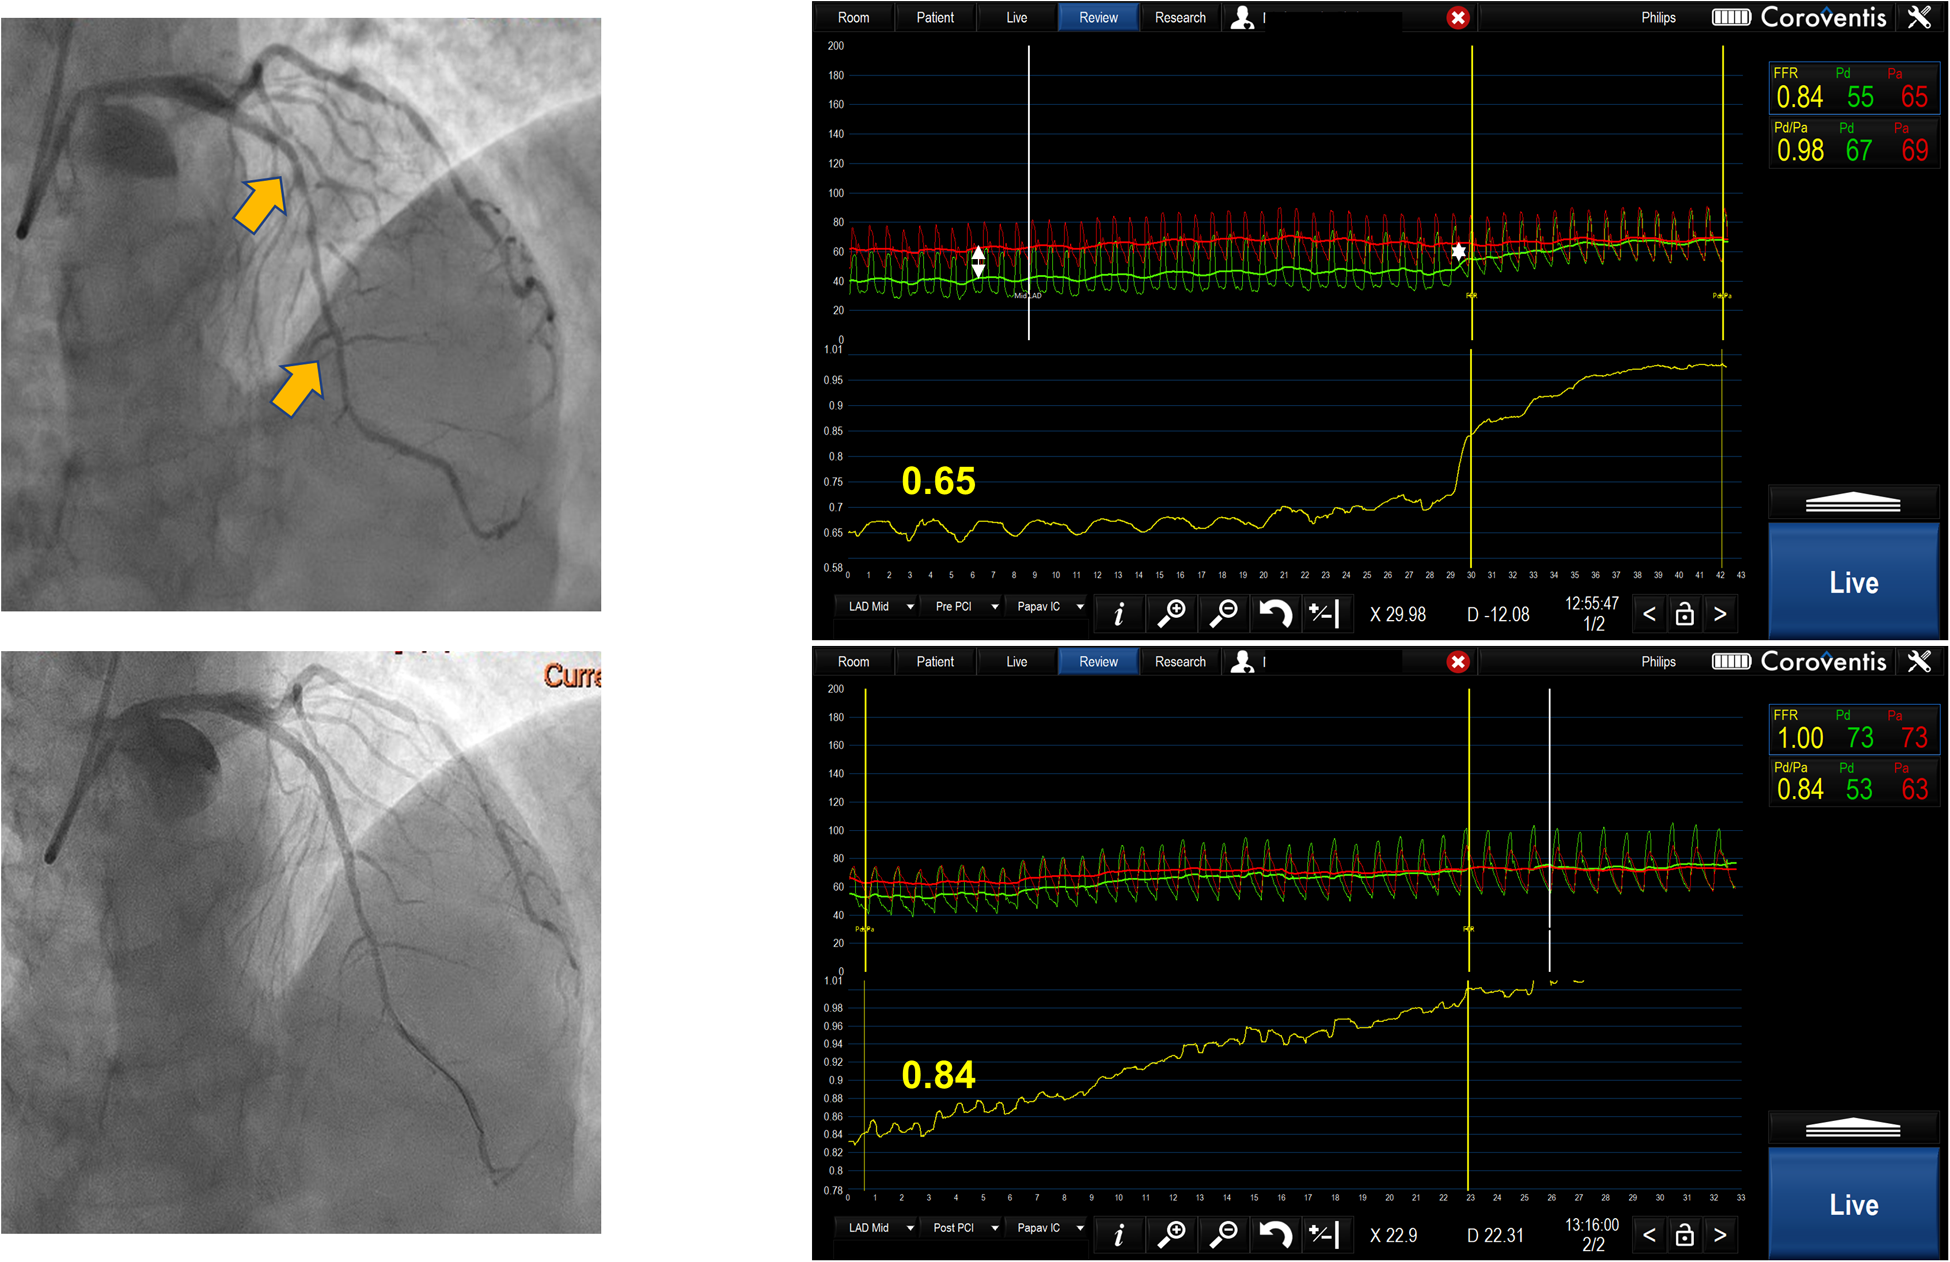

Serial lesion assessment by pullback FFR measurement using Coroventis CoroFlow cardiovascular software (Coroventis AB, Uppsala, Sweden), followed by PCI of the lesion with greatest ΔP and retesting after stent implantation leading to the deferral of further intervention due to an increase in FFR.

FFR pullback can give a trans-stenotic pressure gradient for each lesion constituting tandem lesions. Treating the lesion with the greatest ΔP first and then reevaluating the other lesion is a reasonable approach (Figure 2). This strategy has demonstrated benefits in relatively small registries (12). When treating the lesion with greater ΔP, one might end up stenting long segments of diffusely diseased arteries, which may be revascularized more appropriately by surgical grafting. Further, serial lesion assessment using FFR pullback can lead to an underestimation of each stenosis significance, which may cause misinterpretation in selecting a lesion with a greater ΔP. Also, this technique requires stable hyperemia with intravenous adenosine or intracoronary papaverine with a fixed guiding catheter positioned against the ostium of the artery, which sometimes may be difficult to achieve. Finally, performing manual pullback cannot guarantee steady pullback velocity, which can result in an artificial plateau that can be interpreted as a smaller degree of change in pressure gradient, resulting in stenosis underestimation.